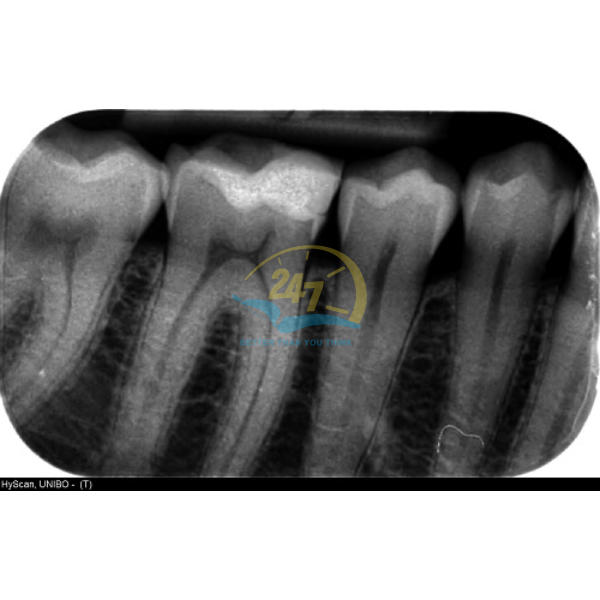

Hình ảnh thu được từ máy quét phim đảm bảo độ chính xác cao, hạn chế tối đa tình trạng mờ, khó nhìn so với công nghệ cũ trước kia. Hơn nữa, thời gian thu được hình ảnh nhanh chóng, chỉ mất vài giây để máy tính xử lý.

Đặc biệt, hình ảnh thu được từ thiết bị chẩn đoán hình ảnh này còn cho phép mở rộng tầm nhìn với sự tương phản hình ảnh rõ rệt. Theo đó, các cấu trúc giải phẫu khác của răng như xương, tủy, chân răng,… đều được thể hiện chính xác trên phim.

Máy quét phim Hy-Scan

Hy-Scan là dòng máy quét phim của hãng Myray (Ý). Thiết bị được thiết kế với kiểu dáng công thái học nhỏ gọn, phù hợp với mọi không gian phòng khám khác nhau.

Đặc biệt, máy quét phim Hy-Scan được trang bị nhiều tính năng hiện đại, đem tới hình ảnh kỹ thuật số với độ sắc nét cao. Ngoài ra, thiết bị tương thích với 4 kích cỡ răng, từ răng sữa đến đỉnh răng, chân răng với chân răng dài, phù hợp với nhiều đối tượng người bệnh khác nhau.